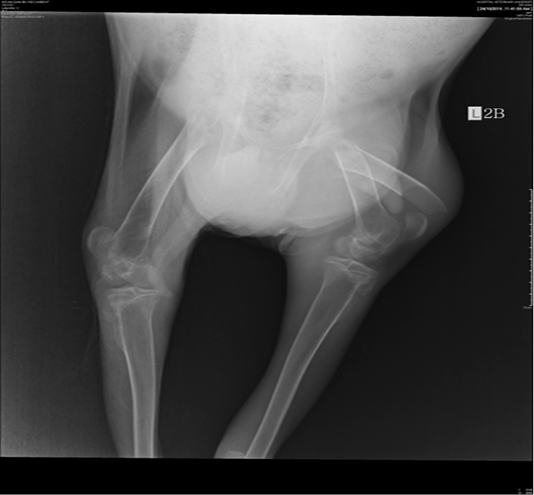

Figure 2

Overriding of the proximal and distal femoral bone fractures on the ventral-dorsal view. Thinning of bone cortex and the presence of increased radiolucency was observed in the bone medulla.